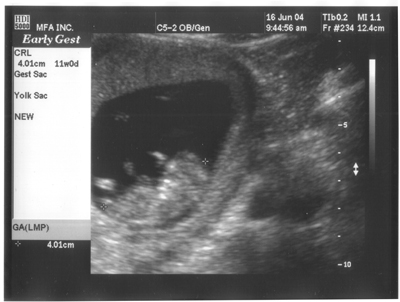

16. Juni 2004